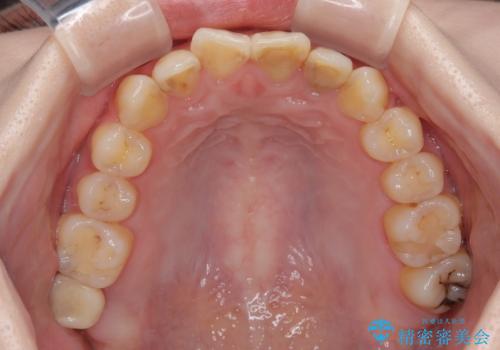

- 過去の歯医者通いの恐怖から虫歯を放置してきたものの、一大決心して来院された患者様です。

神経組織の失活している歯や歯根だけが残っている歯などがあり、全体的に歯石も多く付着している状態でした。

まずは歯石除去とブラッシング方法などの衛生指導を徹底的に行って口腔内環境を改善し、汚れの溜まりやすくなっている親知らずは全て抜去することとしました。

その後、歯根だけとなっている歯はインプラントに、神経組織の失活している歯は根管治療を行い、いずれもオールセラミッククラウンにて補綴治療を行うこととしました。